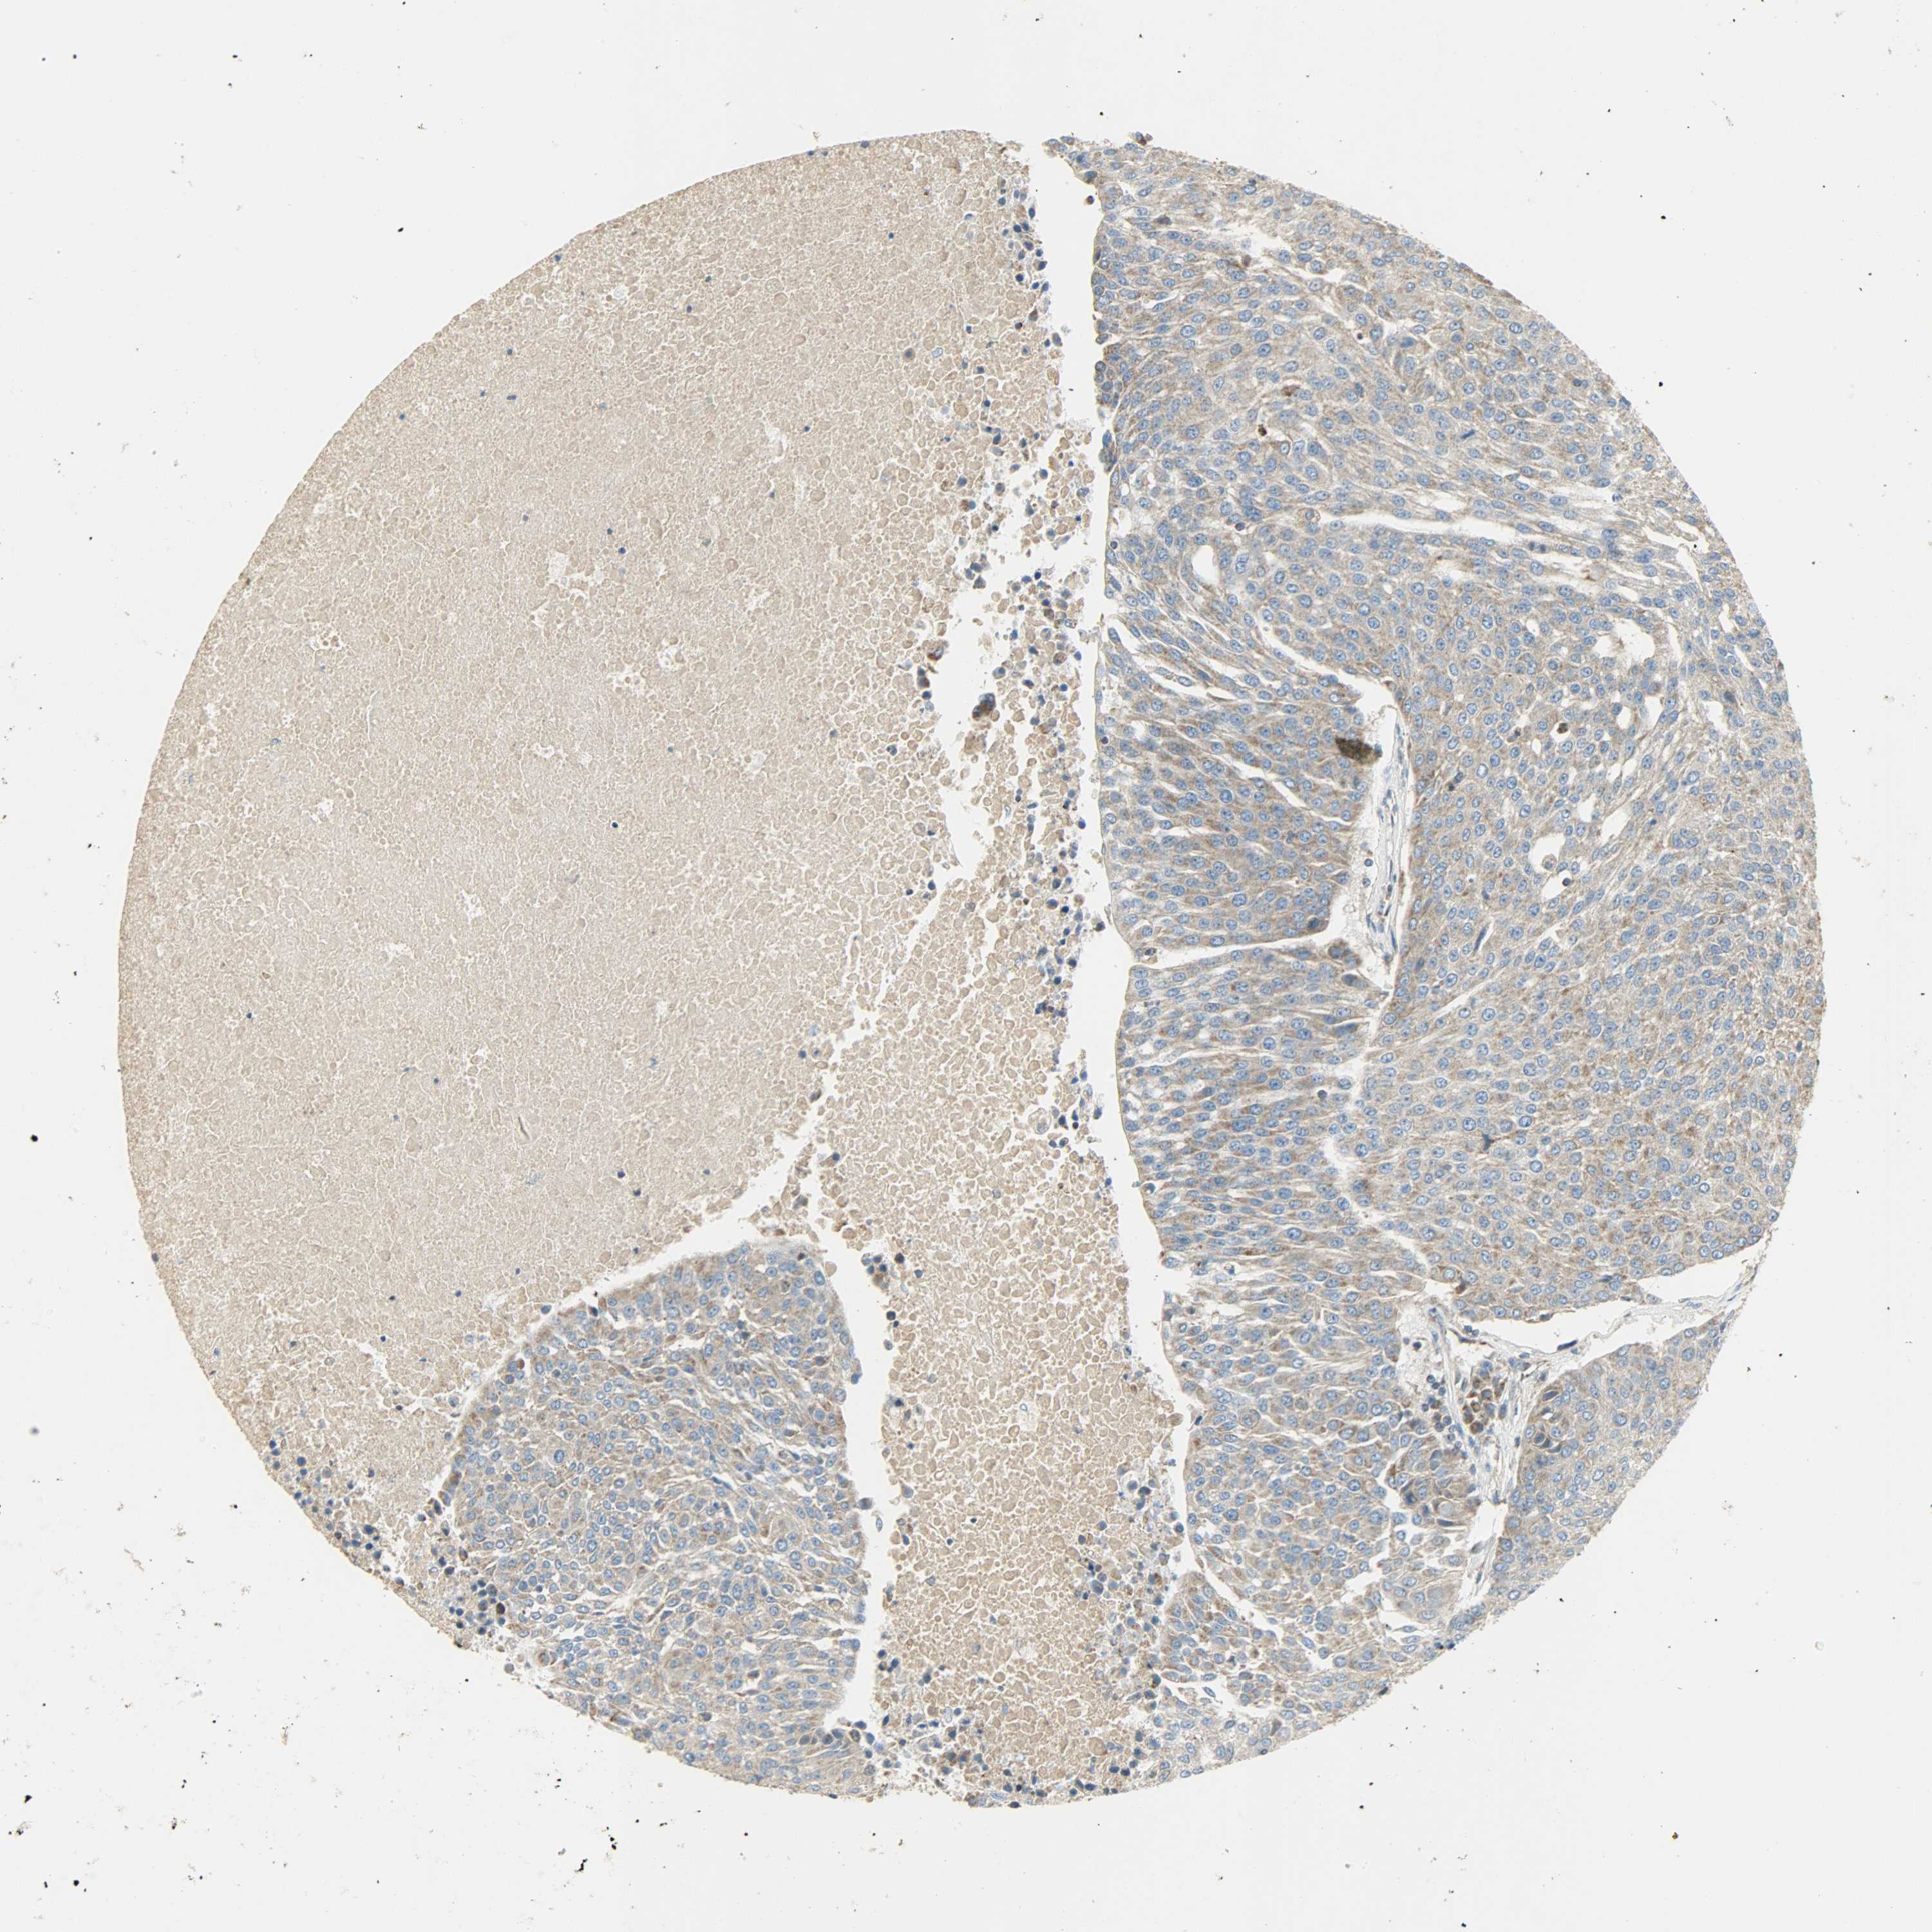

UROTHELIAL CANCER - Protein expressioni

A mouse-over function shows sample information and annotation data. Click on an image to view it in a full screen mode. Samples can be filtered based on level of antibody staining by selecting one or several of the following categories: high, medium, low and not detected. The assay and annotation is described here.

Note that samples used for immunohistochemistry by the Human Protein Atlas do not correspond to samples in the TCGA dataset.

Antibody stainingi

Antibody staining in the annotated cell types in the current human tissue is reported as not detected, low, medium, or high, based on conventional immunohistochemistry profiling in selected tissues. This score is based on the combination of the staining intensity and fraction of stained cells.

Each image is clickable and will lead to virtual microscopy that enables deeper exploration of all samples and also displays staining intensity scores, fraction scores and subcellular localization as well as patient and tissue information for each sample.

Antibody HPA004829

Antibody CAB004975

Urothelial carcinoma, High grade

Urothelial carcinoma, Low grade